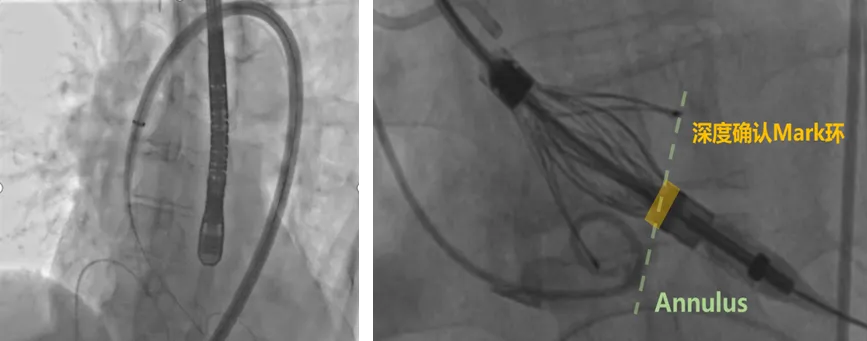

深度检查

深度确认